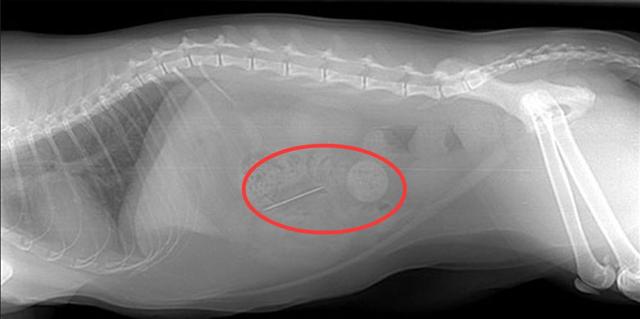

05 食入异物

猫猫很容易误食一些异物:

● 针线

● 绳子和橡皮筋

● 小圆物件

● 骨头